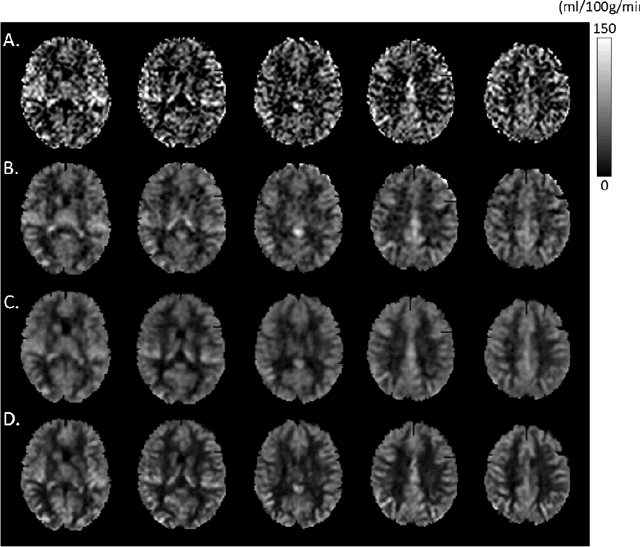

Abstract:Arterial spin labeling (ASL) perfusion MRI provides a non-invasive way to quantify cerebral blood flow (CBF) but it still suffers from a low signal-to-noise-ratio (SNR). Using deep machine learning (DL), several groups have shown encouraging denoising results. Interestingly, the improvement was obtained when the deep neural network was trained using noise-contaminated surrogate reference because of the lack of golden standard high quality ASL CBF images. More strikingly, the output of these DL ASL networks (ASLDN) showed even higher SNR than the surrogate reference. This phenomenon indicates a learning-from-noise capability of deep networks for ASL CBF image denoising, which can be further enhanced by network optimization. In this study, we proposed a new ASLDN to test whether similar or even better ASL CBF image quality can be achieved in the case of highly noisy training reference. Different experiments were performed to validate the learning-from-noise hypothesis. The results showed that the learning-from-noise strategy produced better output quality than ASLDN trained with relatively high SNR reference.

Abstract:Arterial spin labeling perfusion MRI is a noninvasive technique for measuring quantitative cerebral blood flow (CBF), but the measurement is subject to a low signal-to-noise-ratio(SNR). Various post-processing methods have been proposed to denoise ASL MRI but only provide moderate improvement. Deep learning (DL) is an emerging technique that can learn the most representative signal from data without prior modeling which can be highly complex and analytically indescribable. The purpose of this study was to assess whether the record breaking performance of DL can be translated into ASL MRI denoising. We used convolutional neural network (CNN) to build the DL ASL denosing model (DL-ASL) to inherently consider the inter-voxel correlations. To better guide DL-ASL training, we incorporated prior knowledge about ASL MRI: the structural similarity between ASL CBF map and grey matter probability map. A relatively large sample data were used to train the model which was subsequently applied to a new set of data for testing. Experimental results showed that DL-ASL achieved state-of-the-art denoising performance for ASL MRI as compared to current routine methods in terms of higher SNR, keeping CBF quantification quality while shorten the acquisition time by 75%, and automatic partial volume correction.